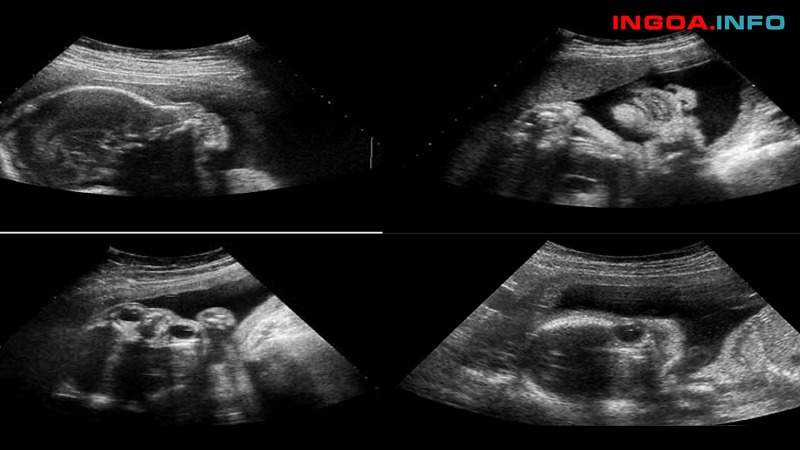

Siêu âm Doppler động mạch rốn:

Ở tam cá nguyệt I, phổ Doppler của động mạch rốn được đặc trưng bởi thiếu vắng dòng chảy cuối tâm trương. Cùng với sự tăng trưởng của thai, cung lượng tim tăng. Cả tốc độ tâm thu lẫn tâm trương trong động mạch cuống rốn đều tăng. Từ tuần thai thứ 18 mở dòng chảy cuối tâm trương.

Tỷ lệ tốc độ cuối tâm thu và tâm trương (S / D ratio) phân phối thông tin về kháng lực mạch máu trong bánh nhau. Bình thường S / D ratio giảm dần về cuối thai kỳ. Vì càng về cuối thai kỳ, nhu yếu dinh dưỡng của thai càng cao, máu đến thai nhi nhiều. Động mạch rốn phải tăng lưu lượng để đưa máu trở về bánh nhau.

- Thai 26 – 30 tuần S / D ratio 4

- Thai 30 – 34 tuần S / D ratio 3,5

- Thai > 34 tuần S / D ratio 3

S / D tăng cao quá số lượng giới hạn được cho phép khi trở kháng bánh nhau tăng cao. Điều này sẽ làm tăng rủi ro tiềm ẩn thai bệnh lý và chết chu sinh .

Người ta đã xác định qua một số ít điều tra ngẫu nhiên là siêu âm Doppler của động mạch rốn trong dân số rủi ro tiềm ẩn cao. Đây là một trắc nghiệm rất hữu dụng. Vắng hay đảo nghịch lưu lượng cuối tâm trương có tương quan đến hậu vận sơ sinh xấu. Tác động ảnh hưởng lâm sàng dựa trên thông tin này. Làm giảm tỷ số chênh của tử trận sơ sinh vào tầm 30 %.

Việc nhìn nhận lưu lượng máu động mạch rốn phải được xem là một trắc nghiệm cơ bản. Để theo dõi thai ở những thai kỳ có rủi ro tiềm ẩn IUGR, hoặc sau chẩn đoán IUGR. Doppler động mạch rốn thai nhi cho thấy tăng dần tỷ số PI đến không đo được, khi mất phổ tâm trương cuối hoặc phổ tâm trương cuối đảo ngược .

Tần suất thai kém tăng trưởng trong tử cung khi mất phổ tâm trương cuối là 94 %, và sẽ tăng lên 100 % khi phổ tâm trương cuối đảo ngược. Tuy nhiên, tín hiệu trên ít có giá trị chẩn đoán sớm trên lâm sàng. Vì PI chỉ tăng một thời hạn lâu sau khi có những tín hiệu rối loạn của thai nhi. Các tài liệu cho thấy, phần đông những thai vắng hoặc đảo nghịch lưu lượng cuối tâm trương ở động mạch rốn dễ bị giảm oxy máu. Hoặc toan hóa máu mạn, và những đặc tính này tương quan đến chậm tăng trưởng thần kinh trong thai kỳ.